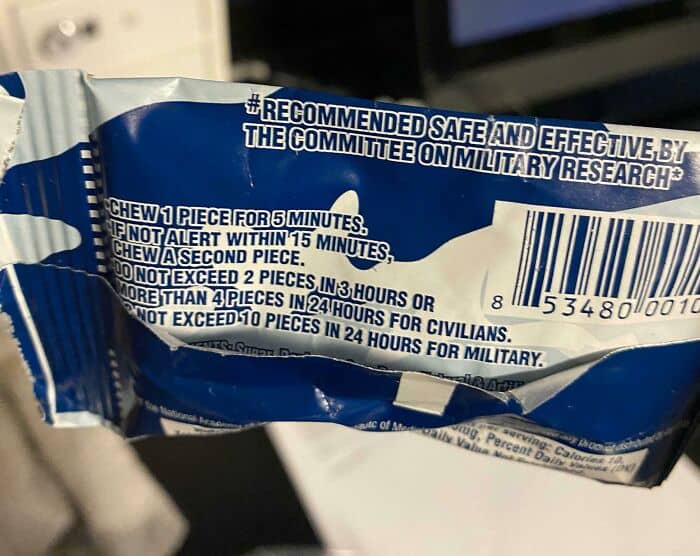

#62 The Amount Of Caffeine Gum That Is “Safe” For Military Members vs. Civilians

#63 My Dog’s Winter Coat vs. Summer Coat